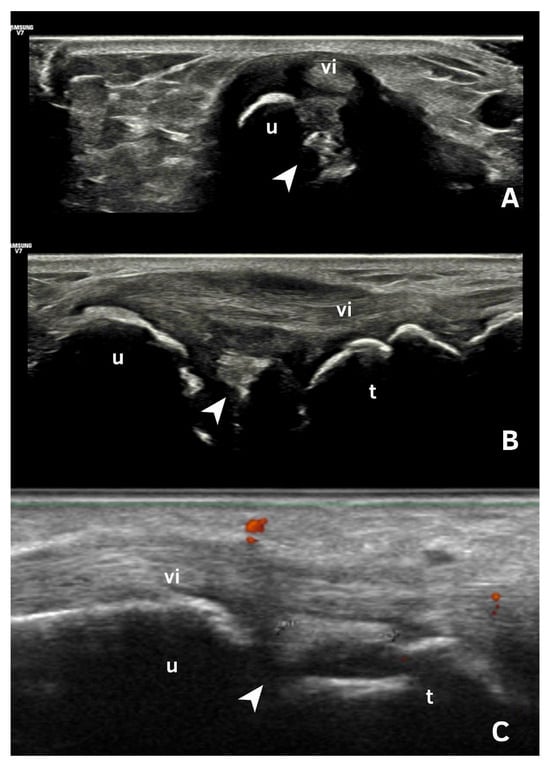

| Fibrocartilage | Shape: Deposits of variable shape. Echogenicity: Hyperechoic (similar to the bone cortex echogenicity). Localization: Within the fibrocartilage structure. Dynamic scanning: Remain fixed and move together with the fibrocartilage during dynamic assessment. Examples: Menisci, TFC, hip labrum, and acromioclavicular joint. |

| Pseudo-double contour sign | Shape: Deposits of variable shape. Echogenicity: Hyperechoic, without posterior shadowing. Localization: Localized at the chondro-synovial interface or in the joint capsule and adjacent ligaments. Dynamic scanning: Moves in the opposite direction of cartilage and adjacent bone. Examples: Knee, proximal, and distal radio-ulnar joint. |